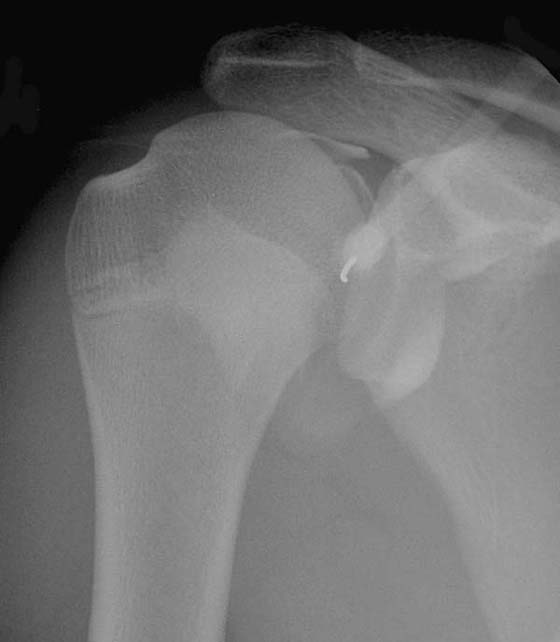

Although shoulder impingement is a clinical diagnosis, it has imaging manifestations that are helpful in guiding treatment. Radiography plays a role in the initial examination of impingement. Subacromial spurs, glenohumeral joint osteoarthritis, and evidence of chronic rotator cuff tear with a high riding humeral head may be identified with radiographs,5 which may further influence management decisions (Fig. 14-6). Noncontrast shoulder MRI is frequently employed in the assessment of impingement. Manifestations of impingement, such as subacromial spur, subacromial/subdeltoid (SASD) bursitis, and rotator cuff tears, are all easily demonstrated on MRI.15-17 Features of a rotator cuff tear that can be assessed on MRI include tear type (full vs. partial thickness), tear location, tear dimensions, tear morphology, tear gap/degree of tendon retraction, and the presence of rotator muscle atrophy (Fig. 14-7).

images

Figure 14-6 Chronic rotator cuff tear. Anteroposterior radiograph of the shoulder demonstrates severe narrowing of the acromiohumeral distance (arrow), indicating chronic rotator cuff tear. Marked subacromial spur formation is also seen. An MRI was contraindicated in this patient due to the presence of a cardiac pacemaker.